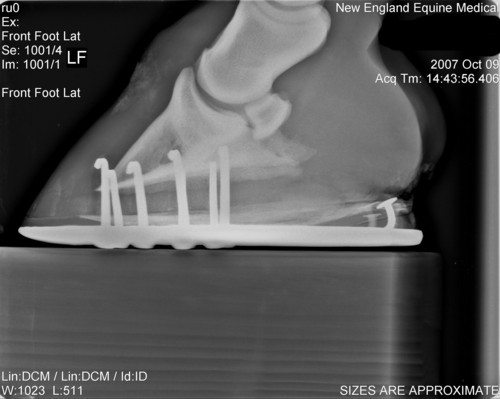

Here are his xrays from about 10-12 weeks ago after the first corrective shoeing. Also included picture of his feet last year before any problems.

Last year

Left AP

Left lat

Right AP

Right Lat

Though I will measure it later, the coffin bone' solar surface angle is acceptable as shod and it should be noted this value does vary greatly among normal horses. Note this is not the same as saying there has been no rotation since the farrier has adjusted the angle with a pad and could have rasped the front wall parallel. We just do not have the information to judge.

Breakover, which is about a cm or two in front of the tip of the coffin bone, looks pretty good though I would prefer a lot more slope to the rocker like that seen in a natural balance shoe. The breakover point of these shoes would disappear on soft ground as the shoe sinks and breakover moves forward to the tip of the foot. Julie would then be right with breakover well too far forward.

Although these images demonstrate the lack of heel and the attempts to correct it, at least the appearance 60 days ago, I would still like to see current images of the foot and sole itself. Your old farrier is correct if the horn quality of the wall is poor and/or the wedges overload the heels. The wedges will distort and breakout poor quality horn and pressure overload slows the growth of the wall at these points. I also do believe egg bars help support poor quality heels when used with proper trimming principles and horn care for more on the trimming see Diseases of Horses » Lameness » Diseases of the Hoof » Correcting Long Toe Low Heel Foot Conformation.